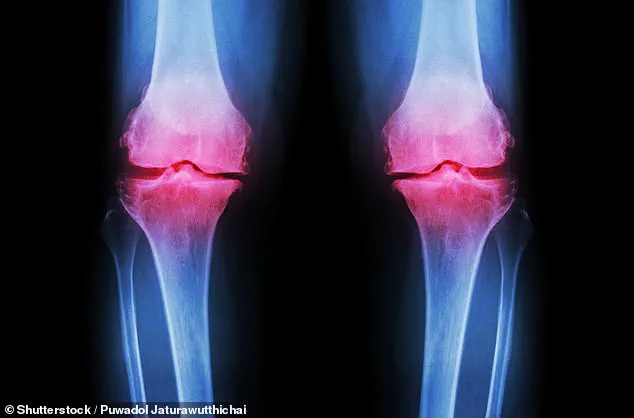

Arthritis, a widespread condition affecting joints across the UK, causes chronic pain, inflammation, and significant mobility challenges.

The condition often arises from cartilage degradation, which occurs naturally over time or as a result of traumatic events such as sports injuries or sudden twists that damage the knee.

Once cartilage is torn or worn down, it lacks the ability to regenerate on its own, leading to progressive joint deterioration.

This deterioration can cause bones to rub against each other, resulting in severe pain, swelling, and even permanent joint deformities.

The condition, which results from the gradual breakdown of cartilage at the ends of bones, leads to pain, swelling, and difficulty in movement as bones rub together.

Articular cartilage, the smooth, rubbery tissue that cushions joints such as the hip, knee, shoulder, and ankle, has long been a medical enigma due to its limited capacity to regenerate after injury or degeneration from aging.

This characteristic has left millions of people worldwide vulnerable to chronic joint pain and conditions like osteoarthritis, which occurs when cartilage erodes to the point that bones grind against each other.